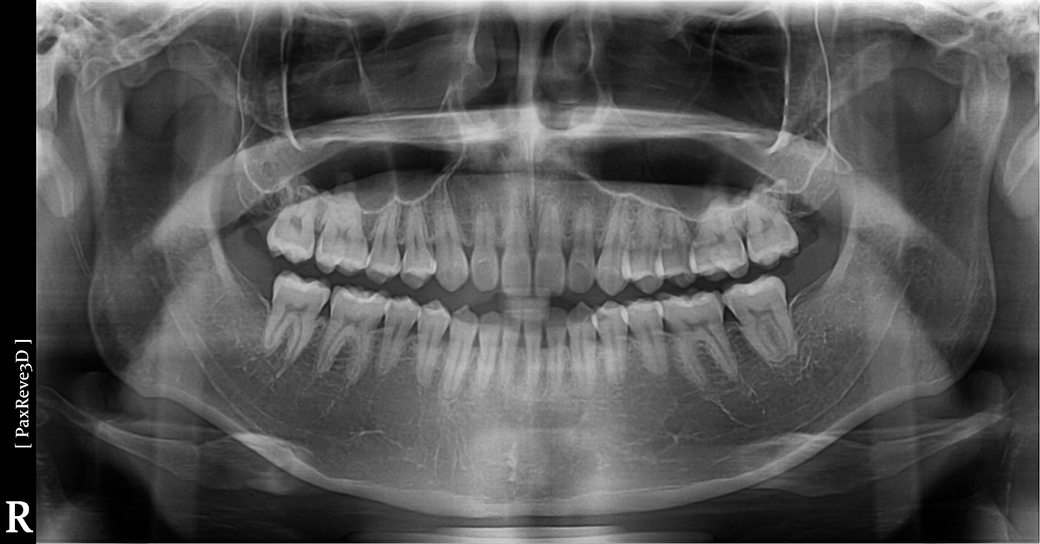

단순히 파노라마 사진만으로는 알 수 없으며 정확히 계측을 해봐야할 것으로 보입니다. 현재 물리는 정도로 불편감이 없다면 지금의 치열배열 상태는 교정에 대상은 아닙니다. 다만 환자분이 불편감을 느끼고 해당 부위에 대한 심미적인 요구가 있다면 할 수는 있습니다. 다만 어떤 교정을 하는 것이 효과적일지는 다각도적인 평가를 더 해보아야 하며 교정 치과 방문 후 상담이 필요합니다.